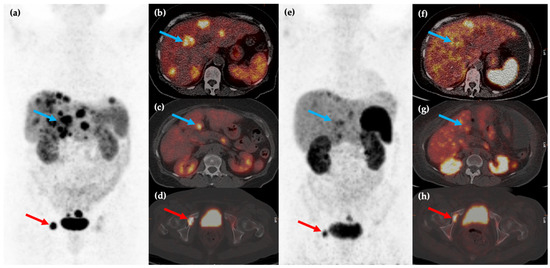

These two studies showed that PRRT with 177Lu-DOTATATE can be an effective treatment, providing symptomatic benefit whilst being well-tolerated and with low levels of toxicity, although it should be noted that complete response to this treatment remains rare. A meta-analysis of six separate studies with 473 patients concluded that 177Lu-DOTATATE is an effective treatment for patients with inoperable or metastatic NENs, with disease response rates ranging between 7% and 43.8% and disease control rates ranging between 73.9% and 100% [79]. The findings of multiple studies led to the eventual approval of 177Lu-DOTATATE by the European Commission and the United States Food and Drug Administration (FDA) and this therapy is now utilized for treatment of metastatic or inoperable well-differentiated (G1 or 2) SSTR positive GEP NENs as a second-line treatment (Figure 3).

Figure 3.

Fifty-year-old female with metastatic G1 NET to liver and bones. 68Ga-DOTATATE PET/CT MIP (a) and axial (b–d) images show multiple sites of SSTR positive hepatic (blue arrows) and osseous (red arrows) disease. The patient was treated with 177Lu-DOTATATE with favorable partial response on post-therapy 68Ga-DOTATATE PET/CT MIP (e) and axial (f–h) images, which show reduction in size and/or number of the previous sites of disease.